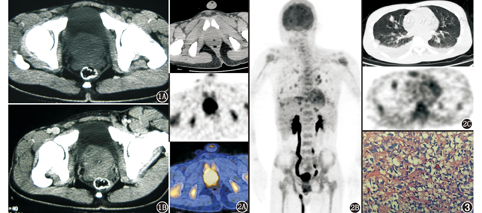

患者男,20岁,2个月前无明显诱因出现腰背疼痛,且进行性加重,出现下肢僵直感。体格检查示精神疲软、贫血貌、消瘦,无发热、黄疸,浅表淋巴结未触及,相关实验室检查提示贫血,对症处理症状未见明显改善。进一步检查发现铁蛋白749(正常参考值80~130) μg/L,其他血清肿瘤标志物(包括总PSA和游离PSA)均正常。骨髓象提示骨髓转移性肿瘤。CT示两肺及胸膜转移性病灶,前列腺增大(图1)。骨扫描示胸骨、前肋骨代谢略活跃。临床以"转移性肺、骨、胸膜肿瘤"申请行PET/CT检查,以探查原发灶。18F-FDG PET/CT(美国GE公司Discovery16型)显像(图2)示前列腺体积明显增大,放射性摄取呈弥漫性异常增高,SUVmax 7.01;右侧肾盂输尿管全程扩张;全身多处骨骼(以锁骨、胸骨、脊柱、骨盆及双上下肢近端骨为著)FDG代谢活跃,SUVmax 5.59,相应部位CT未见明显骨质破坏;两肺散在斑片样、结节样高摄取灶,SUVmax 3.83;双肺门区可见多发高代谢肿大淋巴结影,最大直径约15 mm,SUVmax 6.64;两侧胸腔可见液性密度影,伴结节样、条带样放射性浓聚影,SUVmax 6.31。PET/CT检查结果提示前列腺癌伴全身广泛转移。前列腺穿刺活组织病理检查(图3)提示为前列腺腺泡状横纹肌肉瘤。免疫组织化学检查示:平滑肌肌动蛋白(部分+),结蛋白(+),肌源性决定因子1(+),酸性钙结合蛋白S-100(-),CD99(-),上皮膜抗原(-),人黑色素瘤相关抗原(-)。